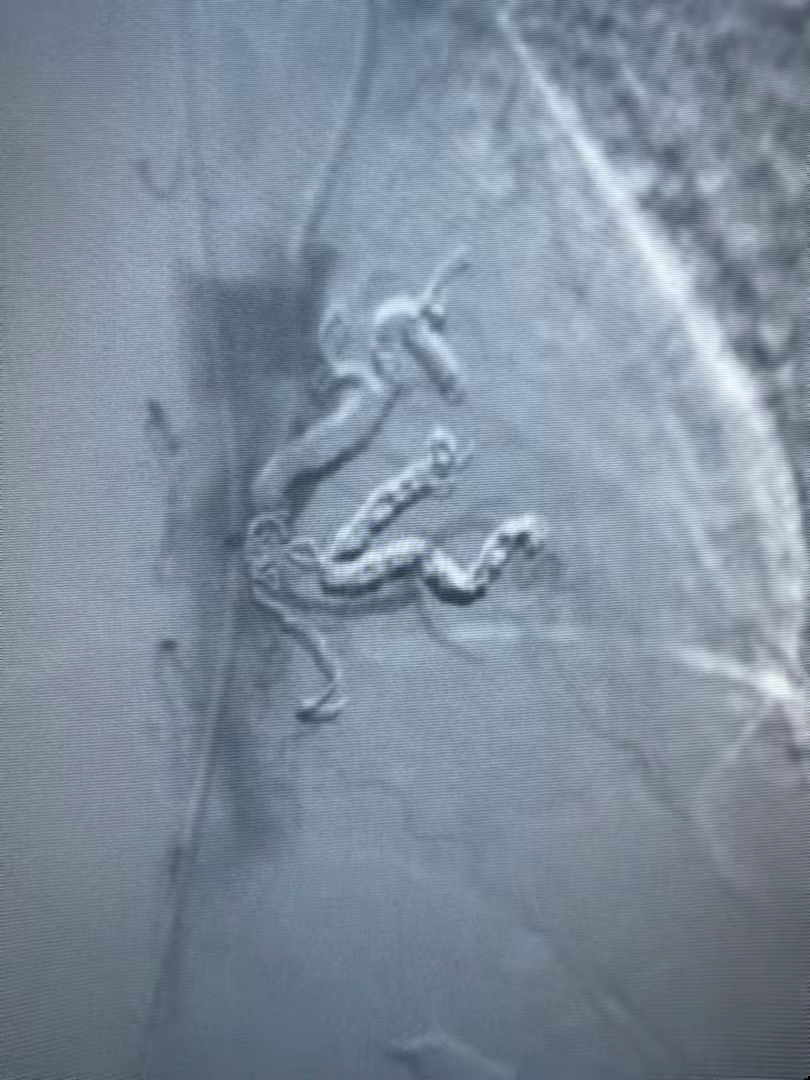

近日,門診收治了一位咯血的老奶奶到介入血管科。時逢周六,醫(yī)生出于安全考慮立即安排增強CT,檢查提示肺隔離癥。這一較為少見的先天性疾病,既往治療以外科手術(shù)切除病變組織為主,考慮到患者年紀大,外科手術(shù)風(fēng)險大,介入血管科團隊經(jīng)慎重考慮予以實施血管栓塞術(shù)。在局麻下經(jīng)股動脈穿刺引入導(dǎo)管與導(dǎo)絲,導(dǎo)管與導(dǎo)絲配合插管至肺隔離癥的供血動脈內(nèi),經(jīng)造影證實屬于肺隔離癥的供血動脈后,選擇直徑大于各分支動脈20%的金屬彈簧圈,對其進行徹底栓塞。經(jīng)過一個多小時的奮戰(zhàn),終于順利完成手術(shù)。